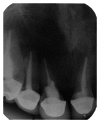

The aim of this case report is to present two cases where cone beam computed tomography (CBCT) was used for the diagnosis, treatment planning, and followup of large periapical lesions in relation to maxillary anterior teeth treated by endodontic surgery. Periapical disease may be detected sooner using CBCT, and their true size, extent, nature, and position can be assessed. It allows clinician to select the most relevant views of the area of interest resulting in improved detection of periapical lesions. CBCT scan may provide a better, more accurate, and faster method to differentially diagnose a solid (granuloma) from a fluid-filled lesion or cavity (cyst). In the present case report, endodontic treatment was performed for both the cases followed by endodontic surgery. Biopsy was done to establish the confirmatory histopathological diagnosis of the periapical lesions. Long-term assessment of the periapical healing following surgery was done in all the three dimensions using CBCT and was found to be more accurate than IOPA radiography. It was concluded that CBCT was a useful modality in making the diagnosis and treatment plan and assessing the outcome of endodontic surgery for large periapical lesions.